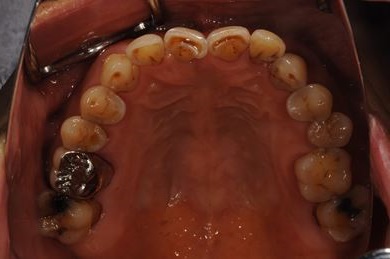

抜歯即日スピードインプラント治療+セラミック治療+歯肉遊離移植術

| 治療内容 | インプラント4本(抜歯即日スピードインプラント)、メタルボンドセラミッククラウン5本、ハイブリッドセラミッククラウン1本(ハイブリッドセラミック用土台1本) | ||||||||||||||||||||||||||||||||

| 治療部位 |